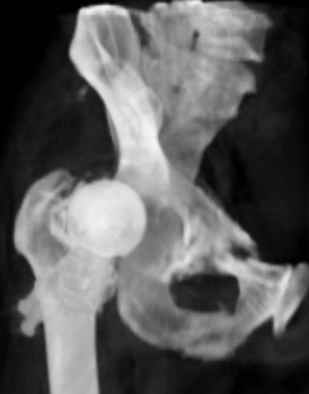

Уважаемые коллеги,Мужчина 1952 г.р. поступил в 36 больницу Екатеринбурга 1 июня 2004 г. Диагноз: Множественный перелом ребер слева, субтотальный гемоторакс, оскольчатый перелом шейки правого бедра.Повреждение таза не диагностировано. 17 июня 2004 г. - открытый остеосинтеза шейки бедра винтами с костной аутопластикой. Заживление раны первичное. Выписан 1 июля. 4 июля отметил укорочение конечности. При контрольном осмотре через 1 месяц после остеосинтеза - передний вывих бедра. Неправильно срастающийся перелом костей таза.Вопрос - особенности эндопртезирования тазобедренного сустава в этой ситуации?

Перелом там от бокового сжания, похоже на LC-I, т.е. компрессионный перелом крестца и на этой же стороне лонной и седалищной. Впадина выглядит совершенно целой. Если там и есть какая-то импрессия в переднем отделе - то микроскопическая.

По видимому снимки н/к сделаны в положении наружной ротации 90гр. И если даже так, то можно определить, что после выполненного остеосинтеза, шейка бедра практически отсутствует.

Даже при нормальной, не поврежденной впадине такое расположение головки относительно большого вертела обречено на вывих (теоретическое или биомеханическое обоснование можно найти в работах Рагозина А.О.).